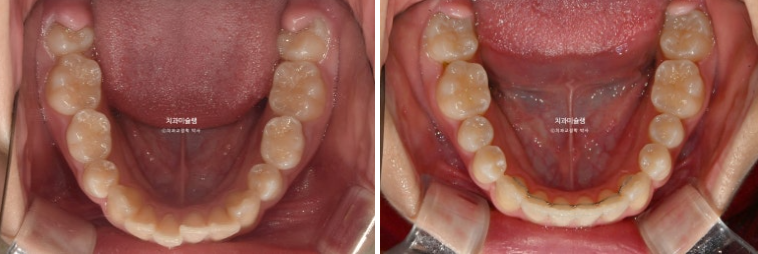

24.09

배열은 좋습니다

25.04

드디어 남은 유치가 다 빠졌습니다.

돌출 개선을 조금 더 도모하고자 두번째 세트 장치 제작에 들어갑니다.

사이즈가 큰 앞니를 미량의 치간삭제를 통해 줄이고 앞니 각도도 좀 더 개선하기로 합니다.

두번째 세트 장치는 15개가 나왔고 25년 11월까지 6개월간 장치를 열심히 껴주고 드디어 치료를 마무리 했습니다.

중심선은 잘 맞고 배열도 좋습니다.

그 사이 마지막 작은어금니까지 모든 영구치가 나와 교합이 완성이 되었습니다.